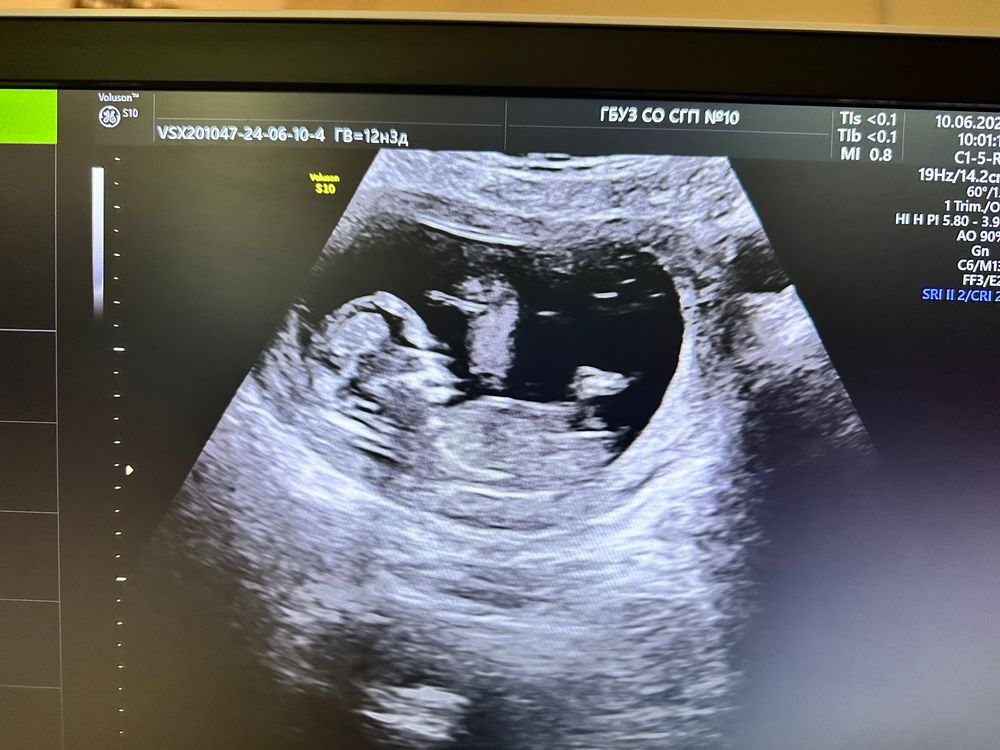

У нас будет девочка!

Поздравляю! Но вы еще раз проверьте на 20ой неделе, а то я тоже целый месяц с девочкой ходила))

Tatiana, 🤣 писюн вырос? С сыном в 14 недель 🥚🍆🥚 на весь экран

Катерина, вот да, у меня тоже вопрос был большой, куда они дели писюн в 16 недель, причем 2 раза). Потом был огромный на весь экран)

Tatiana, акробат, прятал, видимо! Ну я через неделю шейку мерить еще раз, глянут) но я мужу после 1 скрининга сразу сказала, что девочку вижу